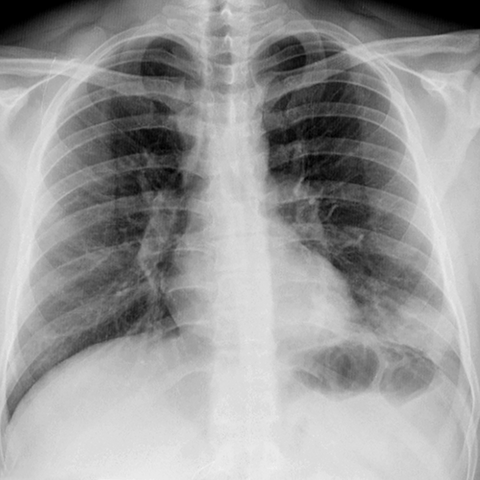

Silhouette Sign, LLL Pneumonia (PA CXR) [1 of 2]